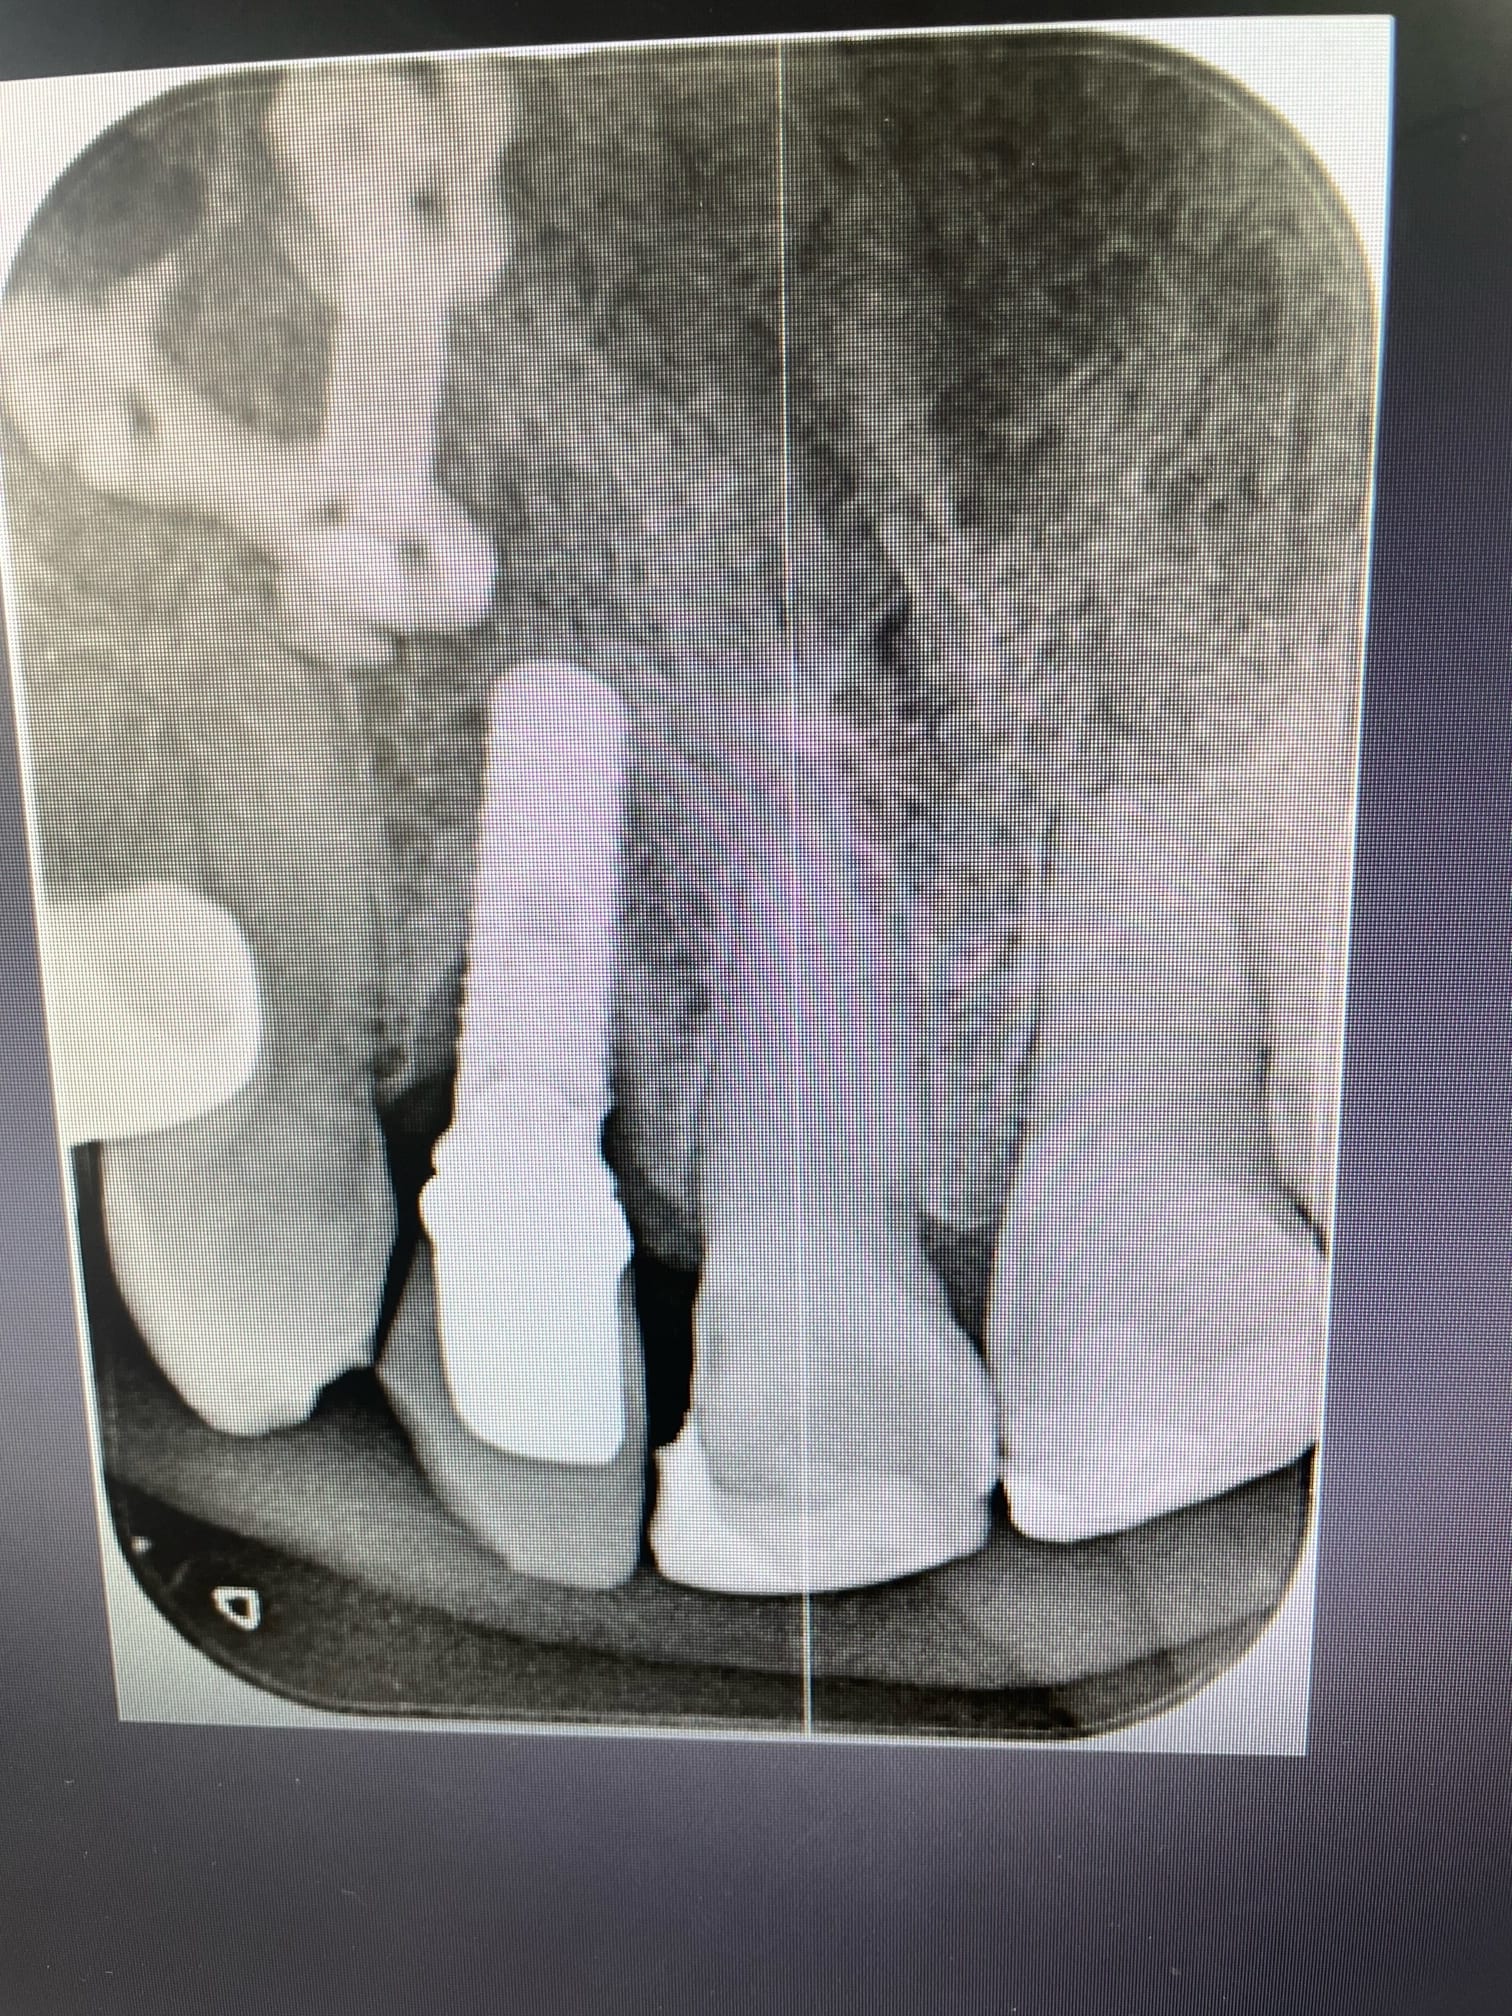

Bonjour, je cherche à confirmer que ces implants sont bien des IDI.

Si oui savez vous avec quelle marque ils sont compatibles et s’il existe des scanbody pour faire de l’empreinte optique?

Des nouvelles de ma galère: les implants sont bien des IDI.

J’ai remis la main sur l’associé du poseur initial. Par contre ce sont des implants qui ont 15 ans. Peut être que la forme a évolué depuis. J’attends la traçabilité exacte la semaine prochaine.

Traçabilité définitive reçue ce matin: IDMAX 4,4. Y a plus qu’à !